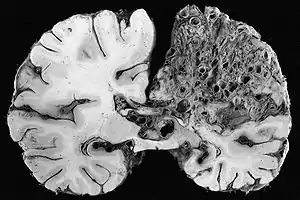

In the brain, AVMs occasionally exert pressure, leading to headaches. They may also increase the risk of seizures, as would any abnormal tissue in the brain. Finally, hemorrhage from an AVM may lead to intracerebral hemorrhage (bleeding into the brain), which causes any of the symptoms of stroke such as weakness in part of the body or difficulty speaking. If the bleeding occurs into the subarachnoid space (subarachnoid hemorrhage), there is usually a severe, sudden headache and decreased level of consciousness and often weakness in part of the body.[1][2]

Brain AVMs may be detected on computed tomography angiography (CTA or CT angio) or magnetic resonance angiography (MRA); CTA is better in showing the vessels themselves, and MRA provides more detail about the relationship between an AVM and surrounding brain tissue.[14] In general, MRI is recommended.[2][7] Various types of vascular malformations may be encountered: AVMs, micro-AVMs, telangiectasias and arteriovenous fistulas.[7] If surgery, embolization, or other treatment is contemplated (see below), cerebral angiography may be required to get sufficient detail of the vessels. This procedure carries a small risk of stroke (0.5%) and is therefore limited to specific circumstances.[7][14] Recent professional guidelines recommend that all children with suspected or definite HHT undergo a brain MRI early in life to identify AVMs that can cause major complications.[7] Others suggest that screening for cerebral AVMs is probably unnecessary in those who are not experiencing any neurological symptoms, because most lesions discovered on screening scans would not require treatment, creating undesirable conundrums.[1]